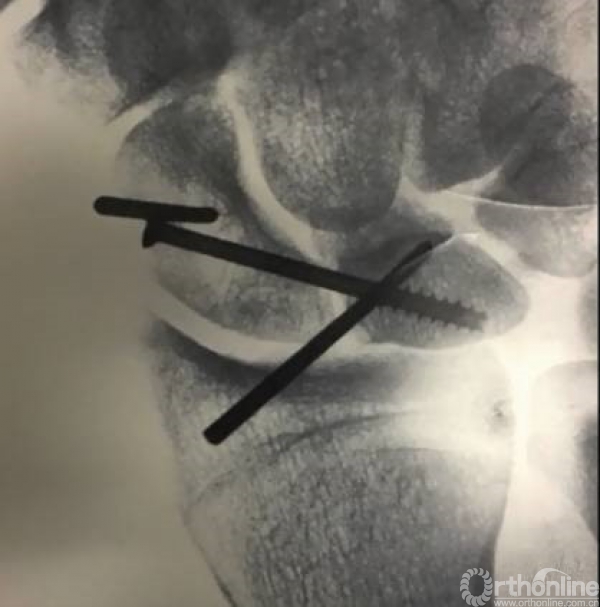

舟骨和月骨各行一个克氏针固定,舟骨从远向近端打,月骨从近向远端打。以供更好的使用摇杆技术进行复位,来进行舟月关节的闭合。

舟骨的克氏针向近端旋转,月骨的克氏针向远端旋转复位后。

复位以后可以用coka把克氏针加持住,然后采用螺钉固定。

透视可见两枚复位克氏针和一枚固定的螺钉,固定螺钉一般采用三层皮质固定舟月微动关节。